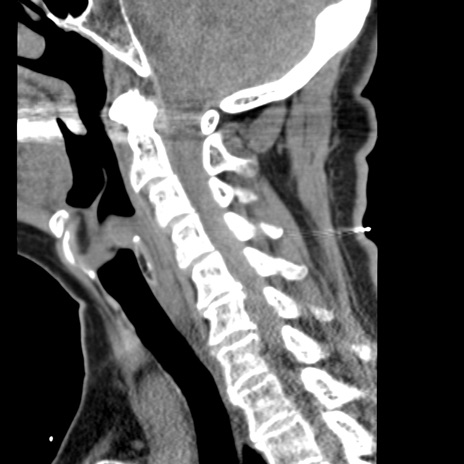

症例50 頚椎CT(矢状断像)

頚椎CT